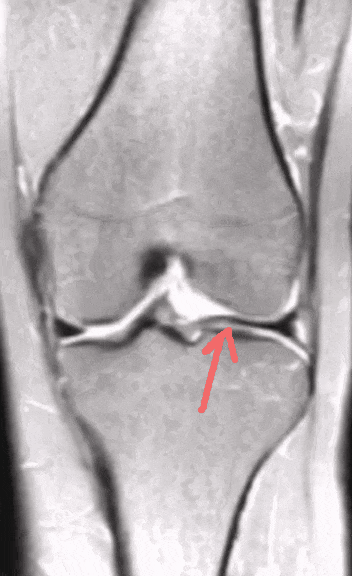

令小张一家感到惊讶的是,医生看到磁共振影像后说,小张的半月板不仅撕裂,而且还存在先天畸形——叫作「盘状半月板」。

从影像上可以看出,小张的半月板比正常人的更大更厚。

正常的半月板,类似「C」字或「O」字型。而盘状半月板,如同盘子一般又圆又厚,因此命名为盘状半月板。